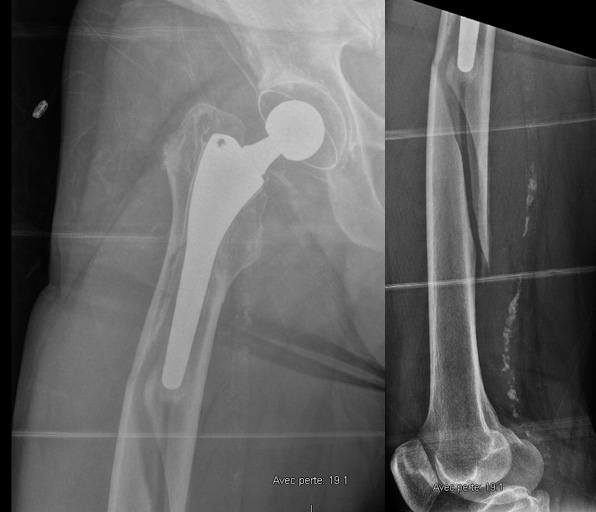

A 71-year-old male, who underwent a right Total Hip Arthroplasty (THA) 12 years ago and a left THA 5 years ago for hip osteoarthritis, recently experienced a fall while walking. Which classification system is appropriate for categorizing the fracture observed in the imagery, and what specific grade? Considering the patient's age, history of bilateral THA, and the nature of the fracture, how would you approach the management of this condition?

• 71 Y.O male

• Right THA 12 years ago and left THA 5 years ago for hip osteoarthritis

• Experienced a fall while walking

Imagery

Which classification allows us to categorize this fracture and what is its grade?

• ✔️Vancouver classification grade B2